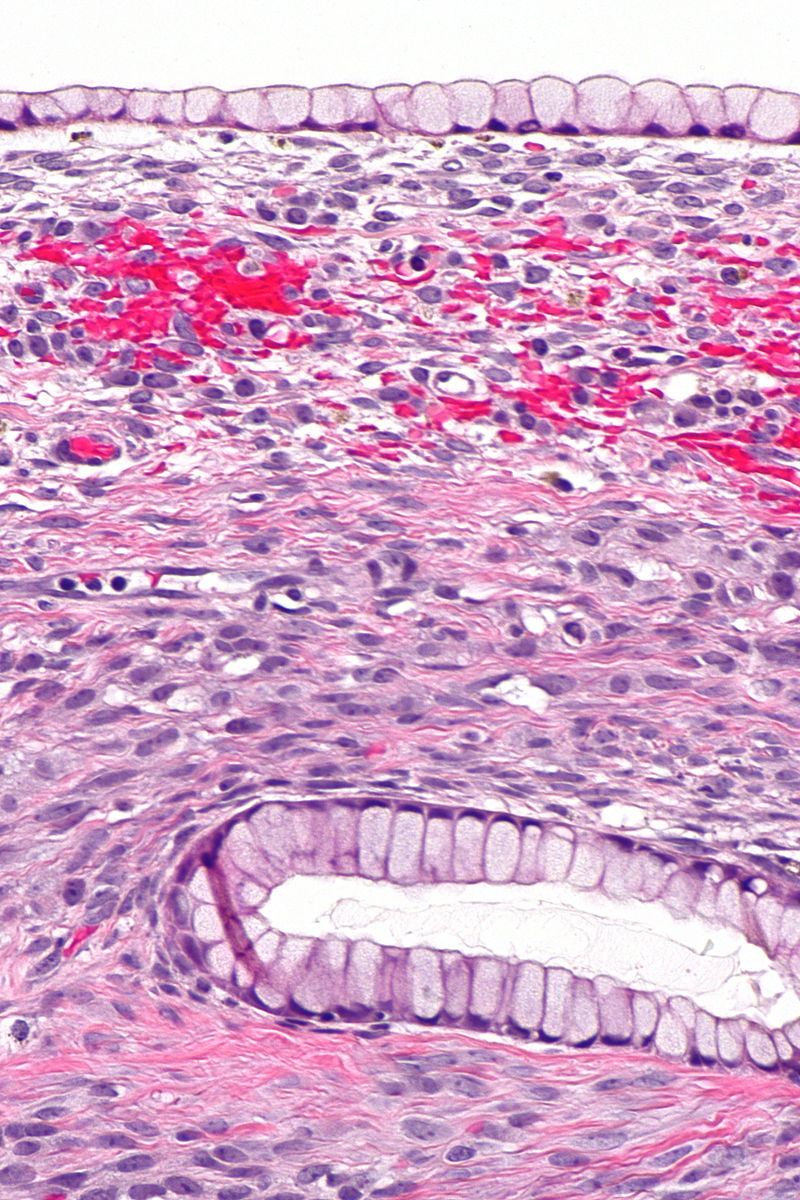

Brenner tumors are typically benign and consist of bladder-like epithelium.